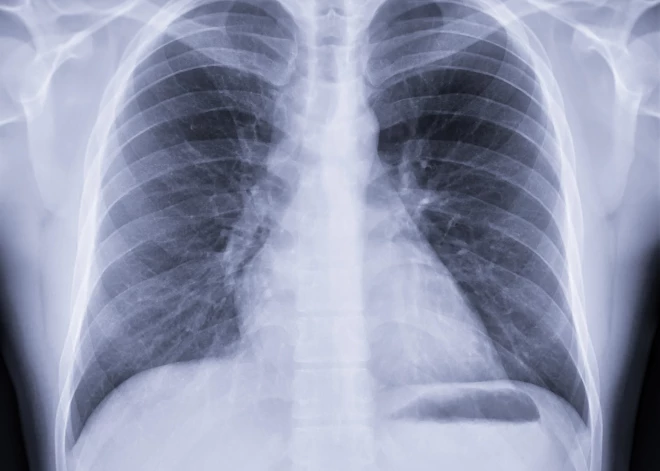

Šogad līdz 28. februārim ir apstiprināti jau 17 legionelozes saslimšanas gadījumi, informē Slimību profilakses un kontroles centrā (SPKC). Legioneloze jeb leģionāru slimība ir legionella baktērijas izraisīta infekcijas slimība. Tā izpaužas kā smaga pneimonija (plaušu karsonis).

- pneimonija

- sāpes krūtīs, apgrūtināta elpošana